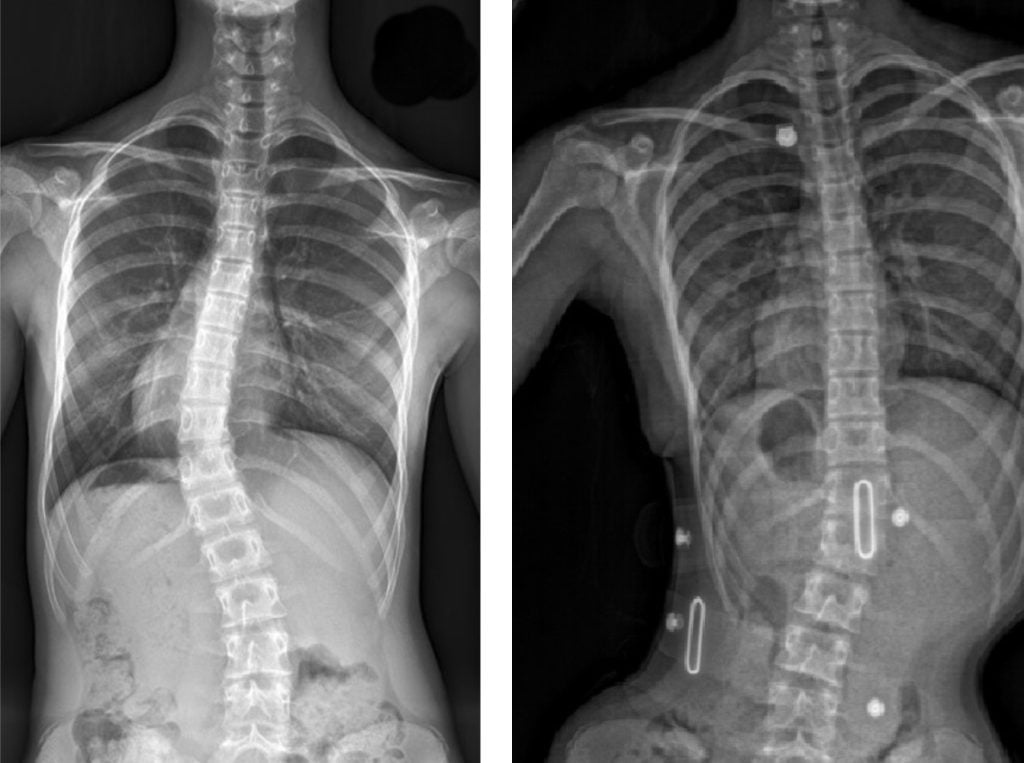

قبل و بعد

حتى أولئك الذين يعانون من اعوجاج العمود الفقري الشديد، حيث تزيد زاوية كوب عن 40 درجة، فقد استجابوا جيدًا لطريقه العلاج التي تعتمد على أحزمه الجنف تشينو-جينسينجن وبرنامج العلاج الطبيعي الذي يتبع مبادئ العلاج الطبيعي في شروث.